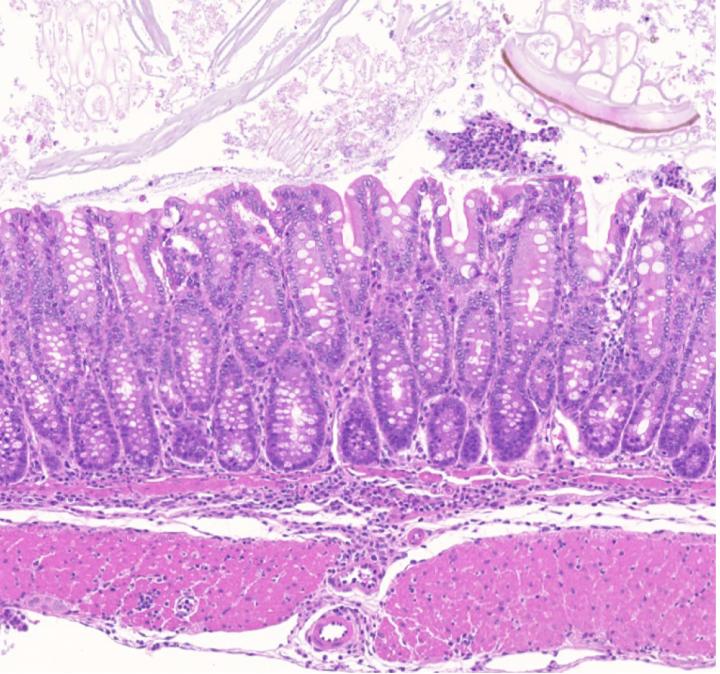

image: Gut inflammation in mice lacking a homologue of a distal enhancer found at the human chromosome 11q13.5 disease risk locus.

The researchers found that the enhancer element controls the expression of a gene in Treg cells, which encodes a protein called GARP (Glycoprotein A Repetitions Predominant). They showed that deleting this enhancer element caused loss of the GARP protein in Treg cells, and an uncontrolled response to a triggered inflammation of the colon lining. This demonstrated that the enhancer is required for Treg-mediated suppression of colitis, with a role for the GARP protein in this immune system control.